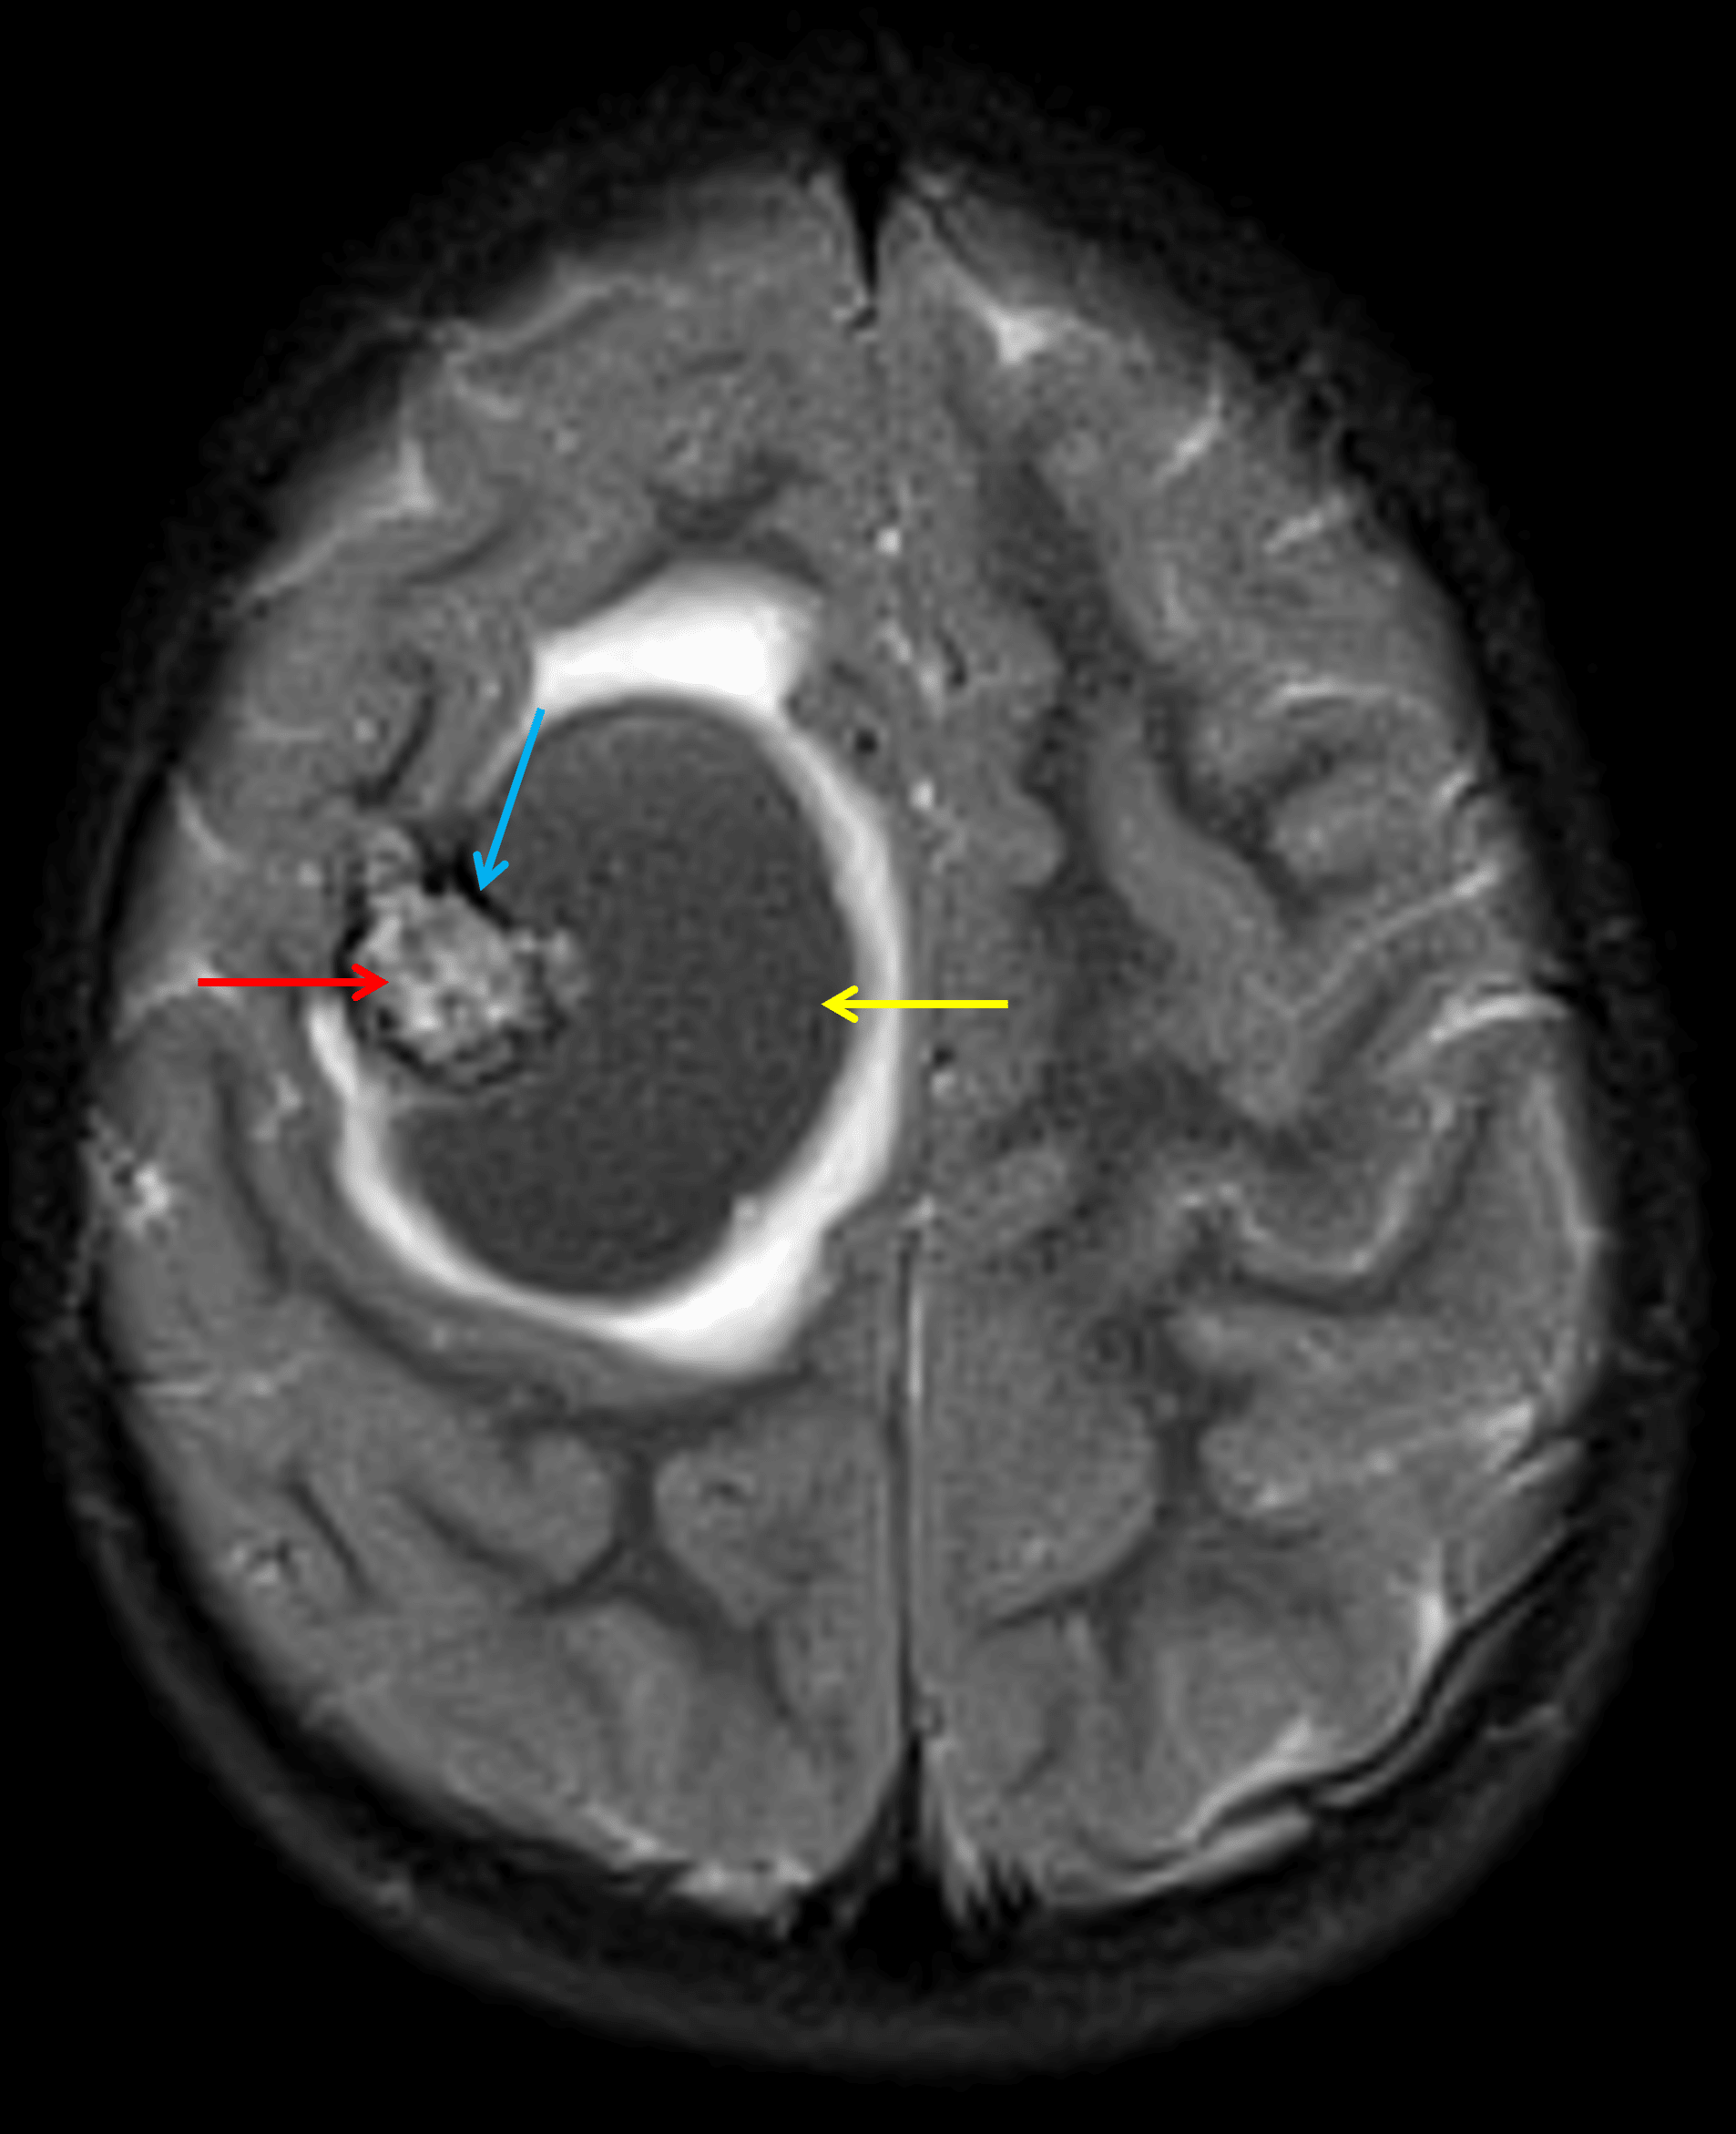

Lesion in the right frontal lobe with heterogeneous internal T2 signal intensity (red arrow), a rim of T2 signal hypointensity (blue arrow), and an adjacent hematoma (yellow arrow) with surrounding edema.